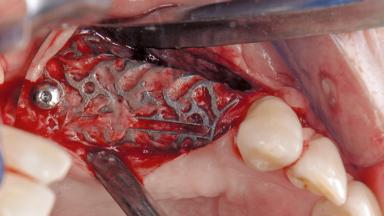

Paolo Casentini and Matteo Chiapasco present a case in which the peri-implant defect was not suitable for a fully regenerative approach. It involves implant removal, use of a CAD/CAM customized titanium mesh in the grafting phase, and placement of new implants. A 62-year-old woman was referred for consultation regarding her implant-supported prosthesis replacing teeth 14 to 16. The patient’s main concern was pain and recurrent swelling in the right posterior maxilla. The patient also reported difficulty and discomfort when brushing the area. The patient reported she had been treated in another country, where she had received three implants in combination with sinus-floor augmentation for the replacement of the posterior maxillary teeth three years earlier. The patient indicated “endodontic complications” to be the reason for the extraction of the teeth.